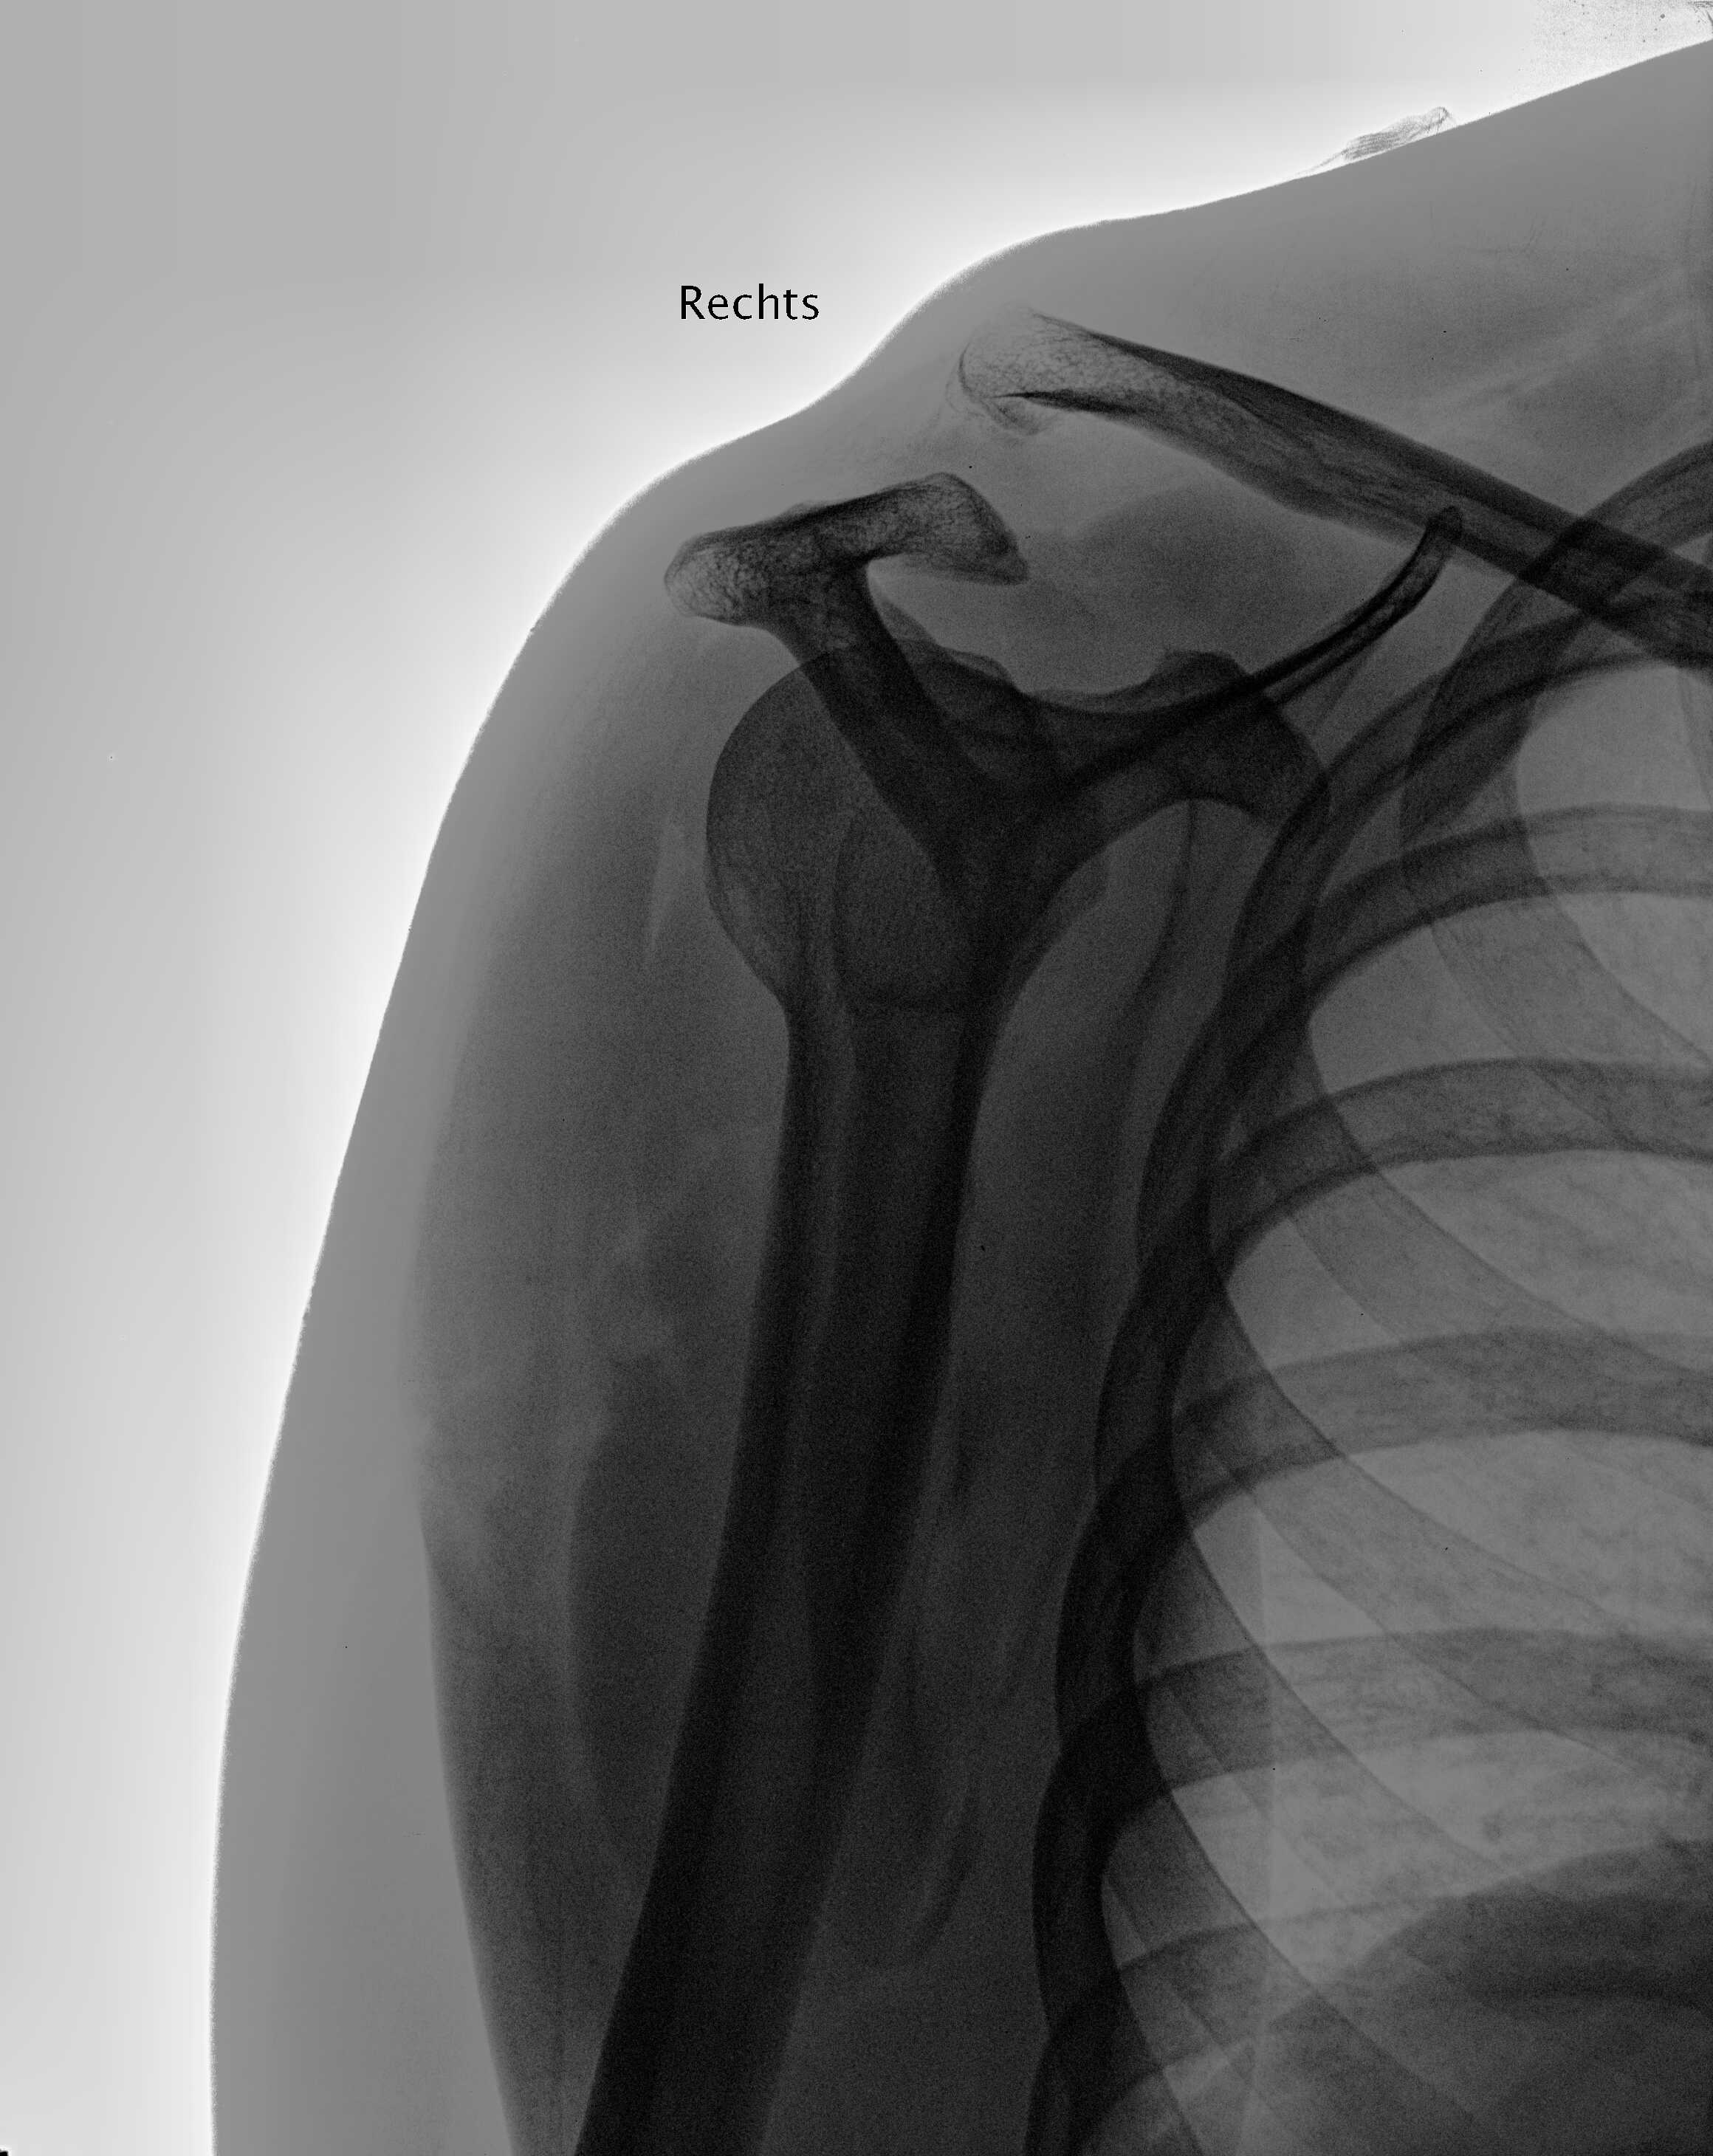

das kommt davon, wenn man sich gleich am ersten urlaubstag in den tiroler bergen mit dem mountainbike austobt

ergebnis: alle bänder gerissen und schulter gebrochen. rettung, op und 12 wochen "krankenkassaurlaub" minimum